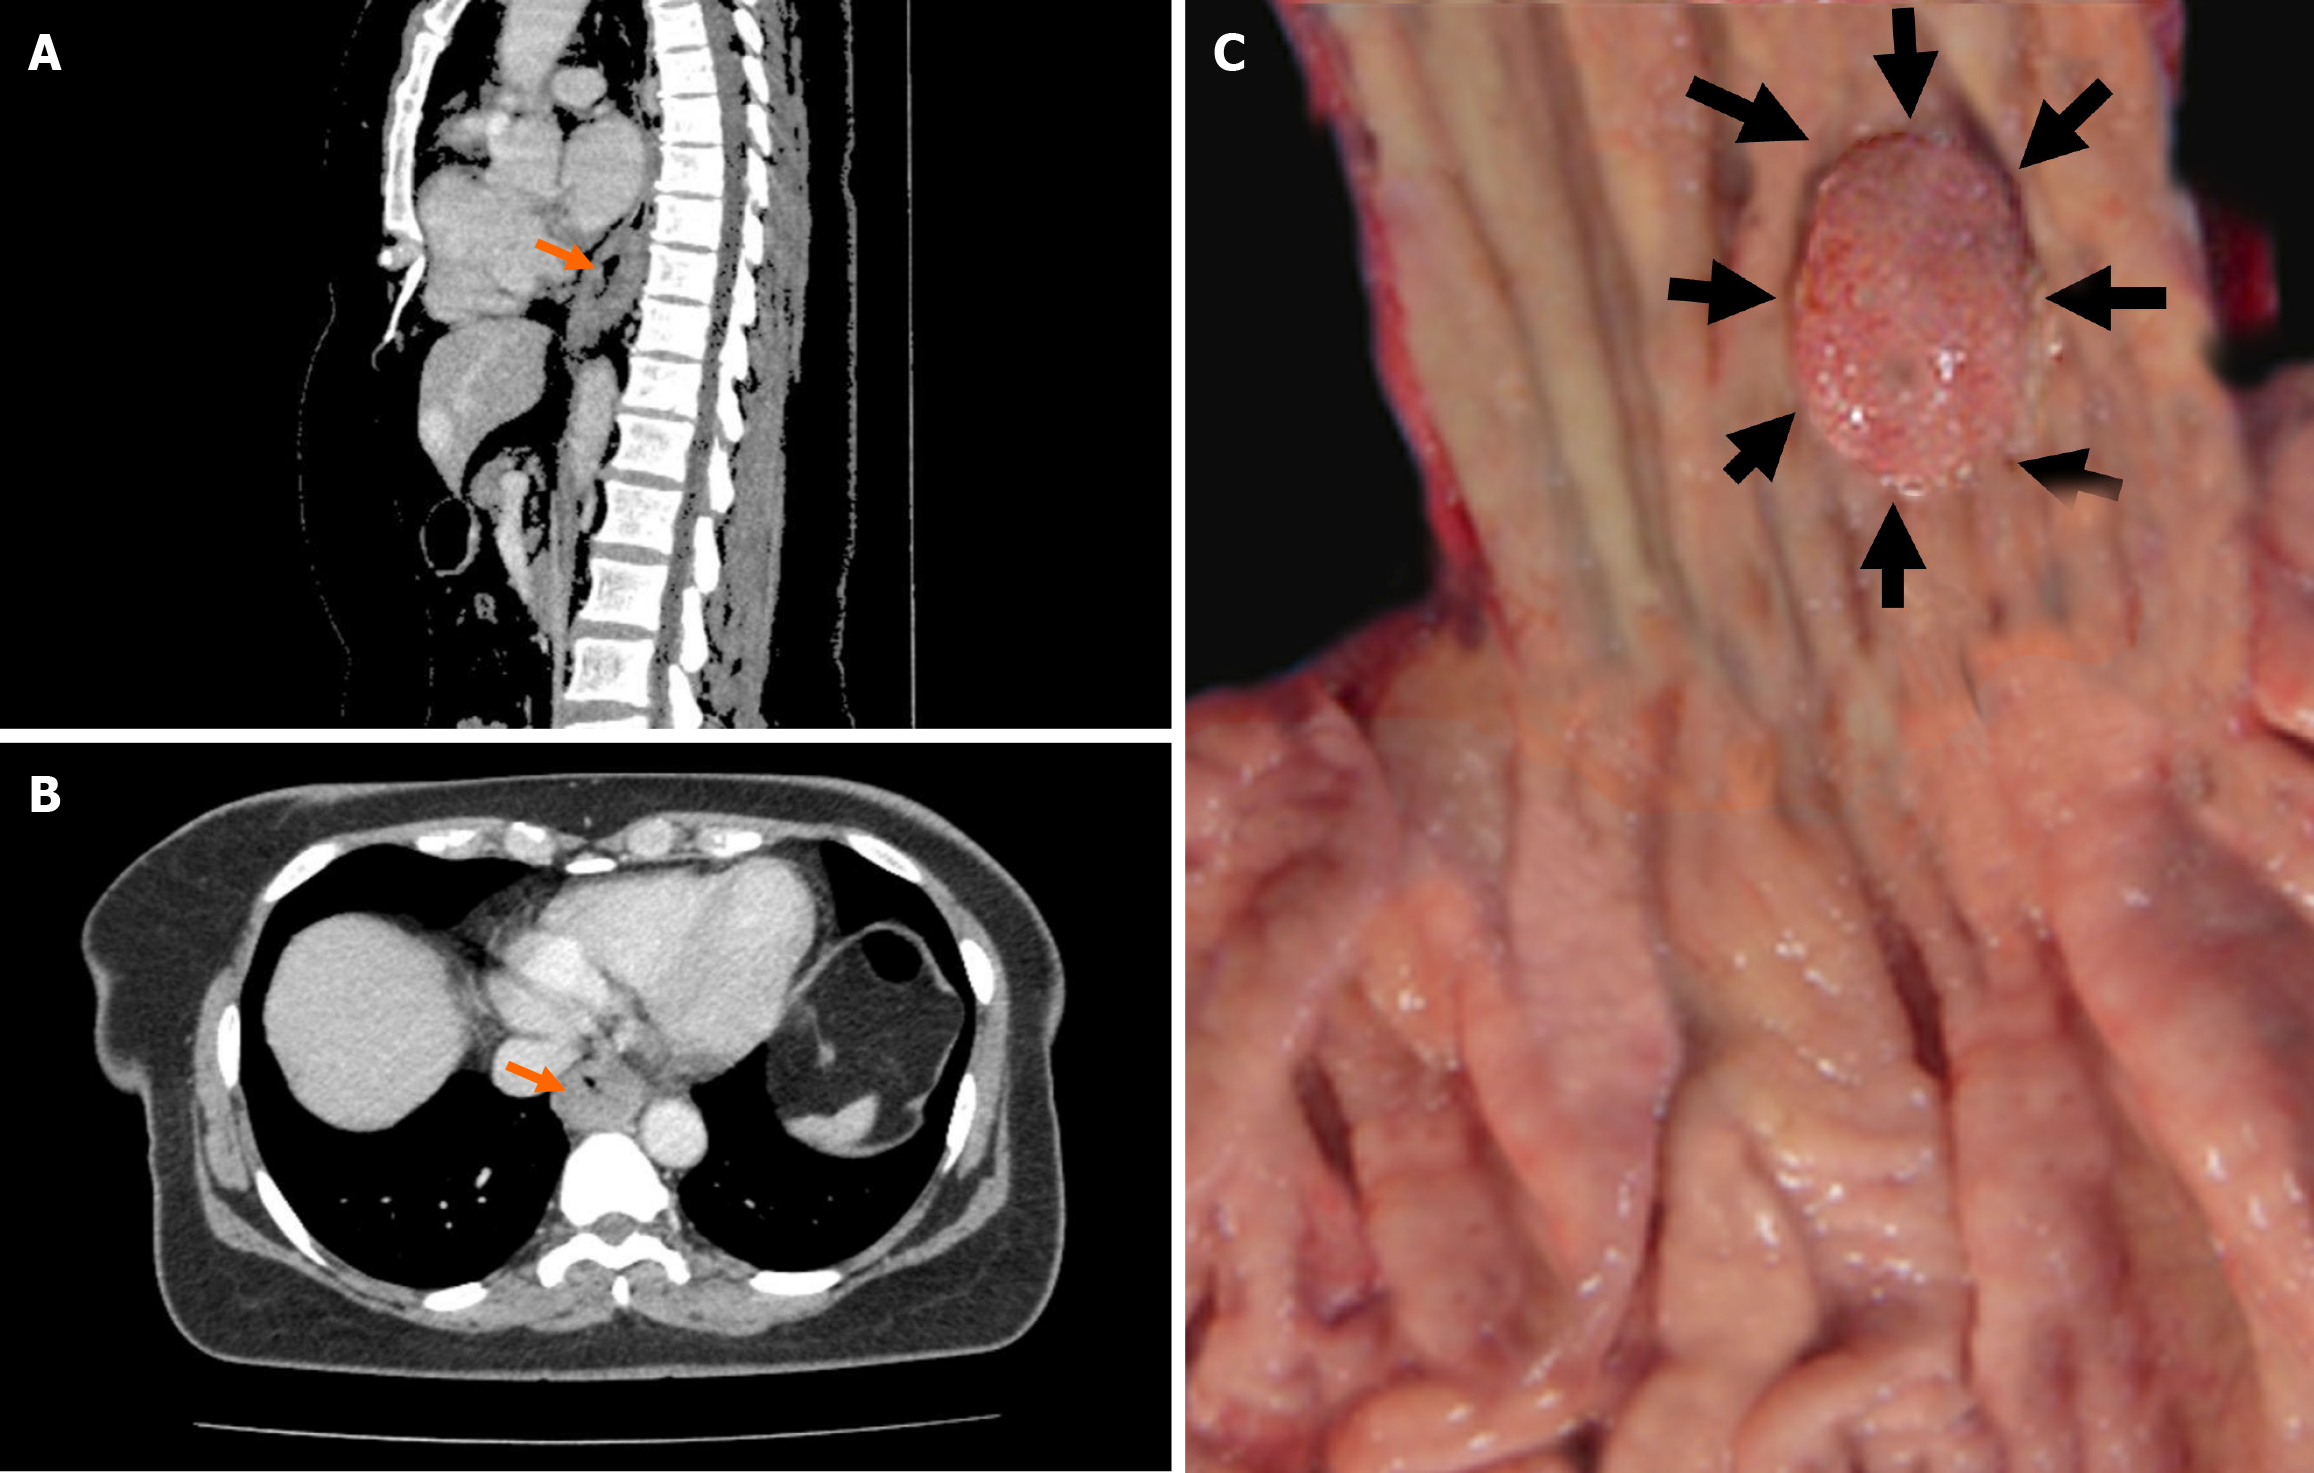

Figure 1 Contrast enhanced computed tomography and macroscopic findings.

A: In the contrast enhanced computed tomography, the sagittal section shows wall thickening in the distal esophagus (orange arrow); B: The axial section reveals wall thickening in the same localization. No lymph node metastasis is observed in either section; C: The macroscopic appearance of the lesion reveals its proximity to the gastroesophageal junction. This location is significant because it can influence both the surgical approach and the overall treatment strategy, given the anatomical and functional importance of the gastroesophageal junction.